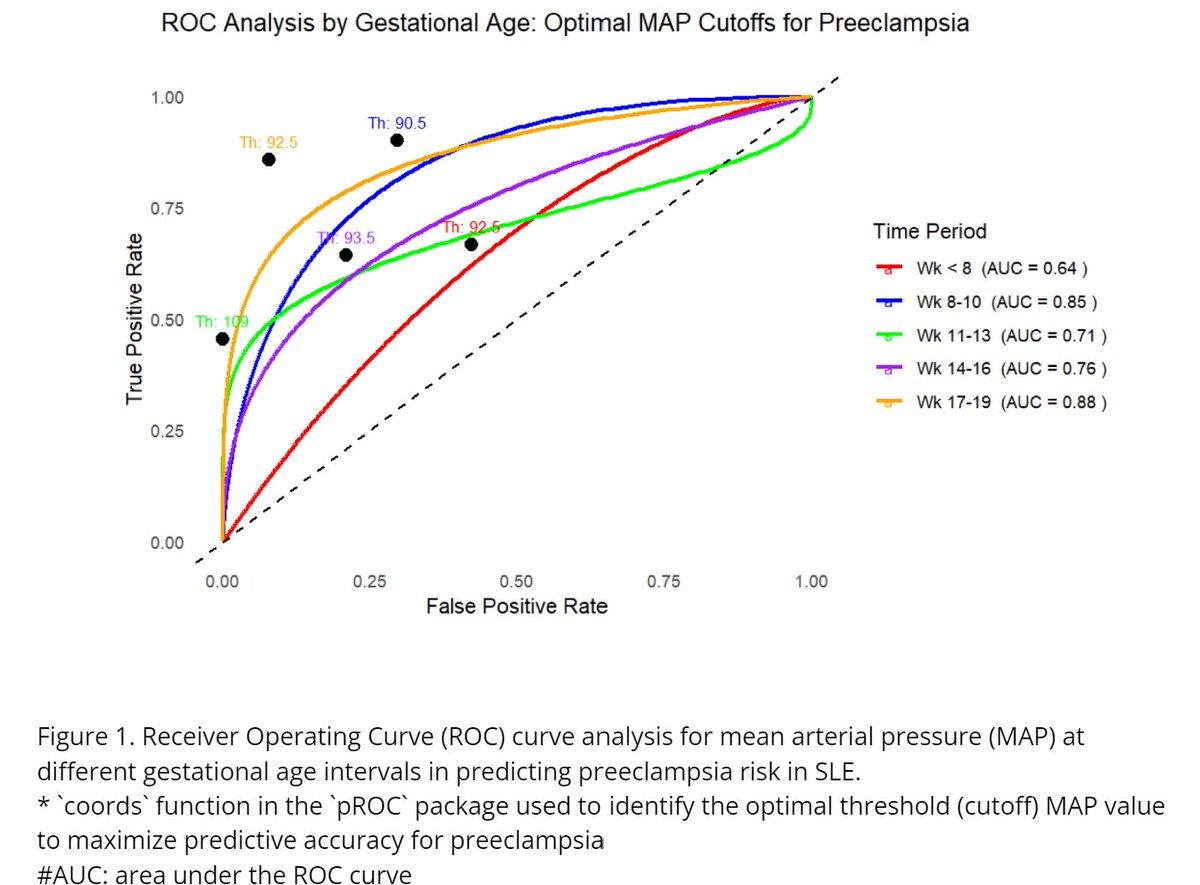

#ACR24 abst#0430

- Analyzed 61 SLE pregnancies

- Higher early gestational Mean Arterial Pressure before 20 Weeks linked to increased preeclampsia risk

- MAP trends at 8-10 and 17-19 weeks showed highest predictive accuracy for risk prediction

@RheumNow https://t.co/37mg0WX43v

Bella Mehta bella_mehta ( View Tweet)